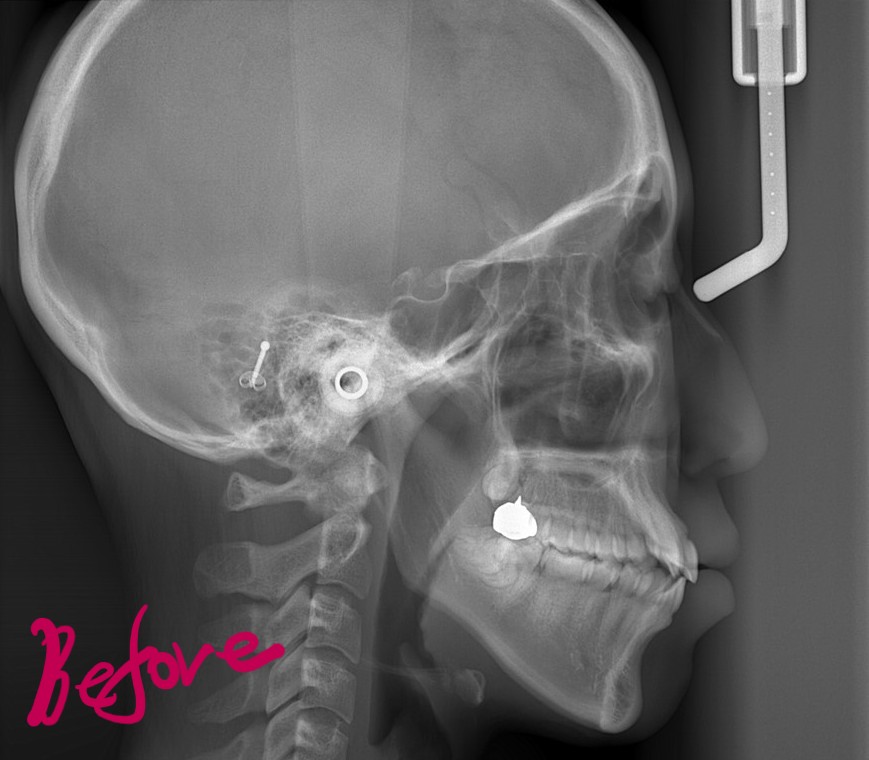

レントゲン写真で確認すると、

この患者さんの場合、

矯正後の状態をレントゲン写真で確認すると、

最後に、矯正治療前後の「レントゲン写真」と「口元の写真」の比較をお見せしましょう。

それでは、その間の変化をレントゲン写真で見てみましょう。

右側が智歯を抜歯してアンカースクリューを併用しながら歯列全体を引っ込めた後の状態、

歯列の途中の奥歯を抜歯するほどには変化させられませんが、智歯という普通は抜歯だけで済ませる歯を利用することで、このように「もう一声!」口元の変化を起こすことも可能です。